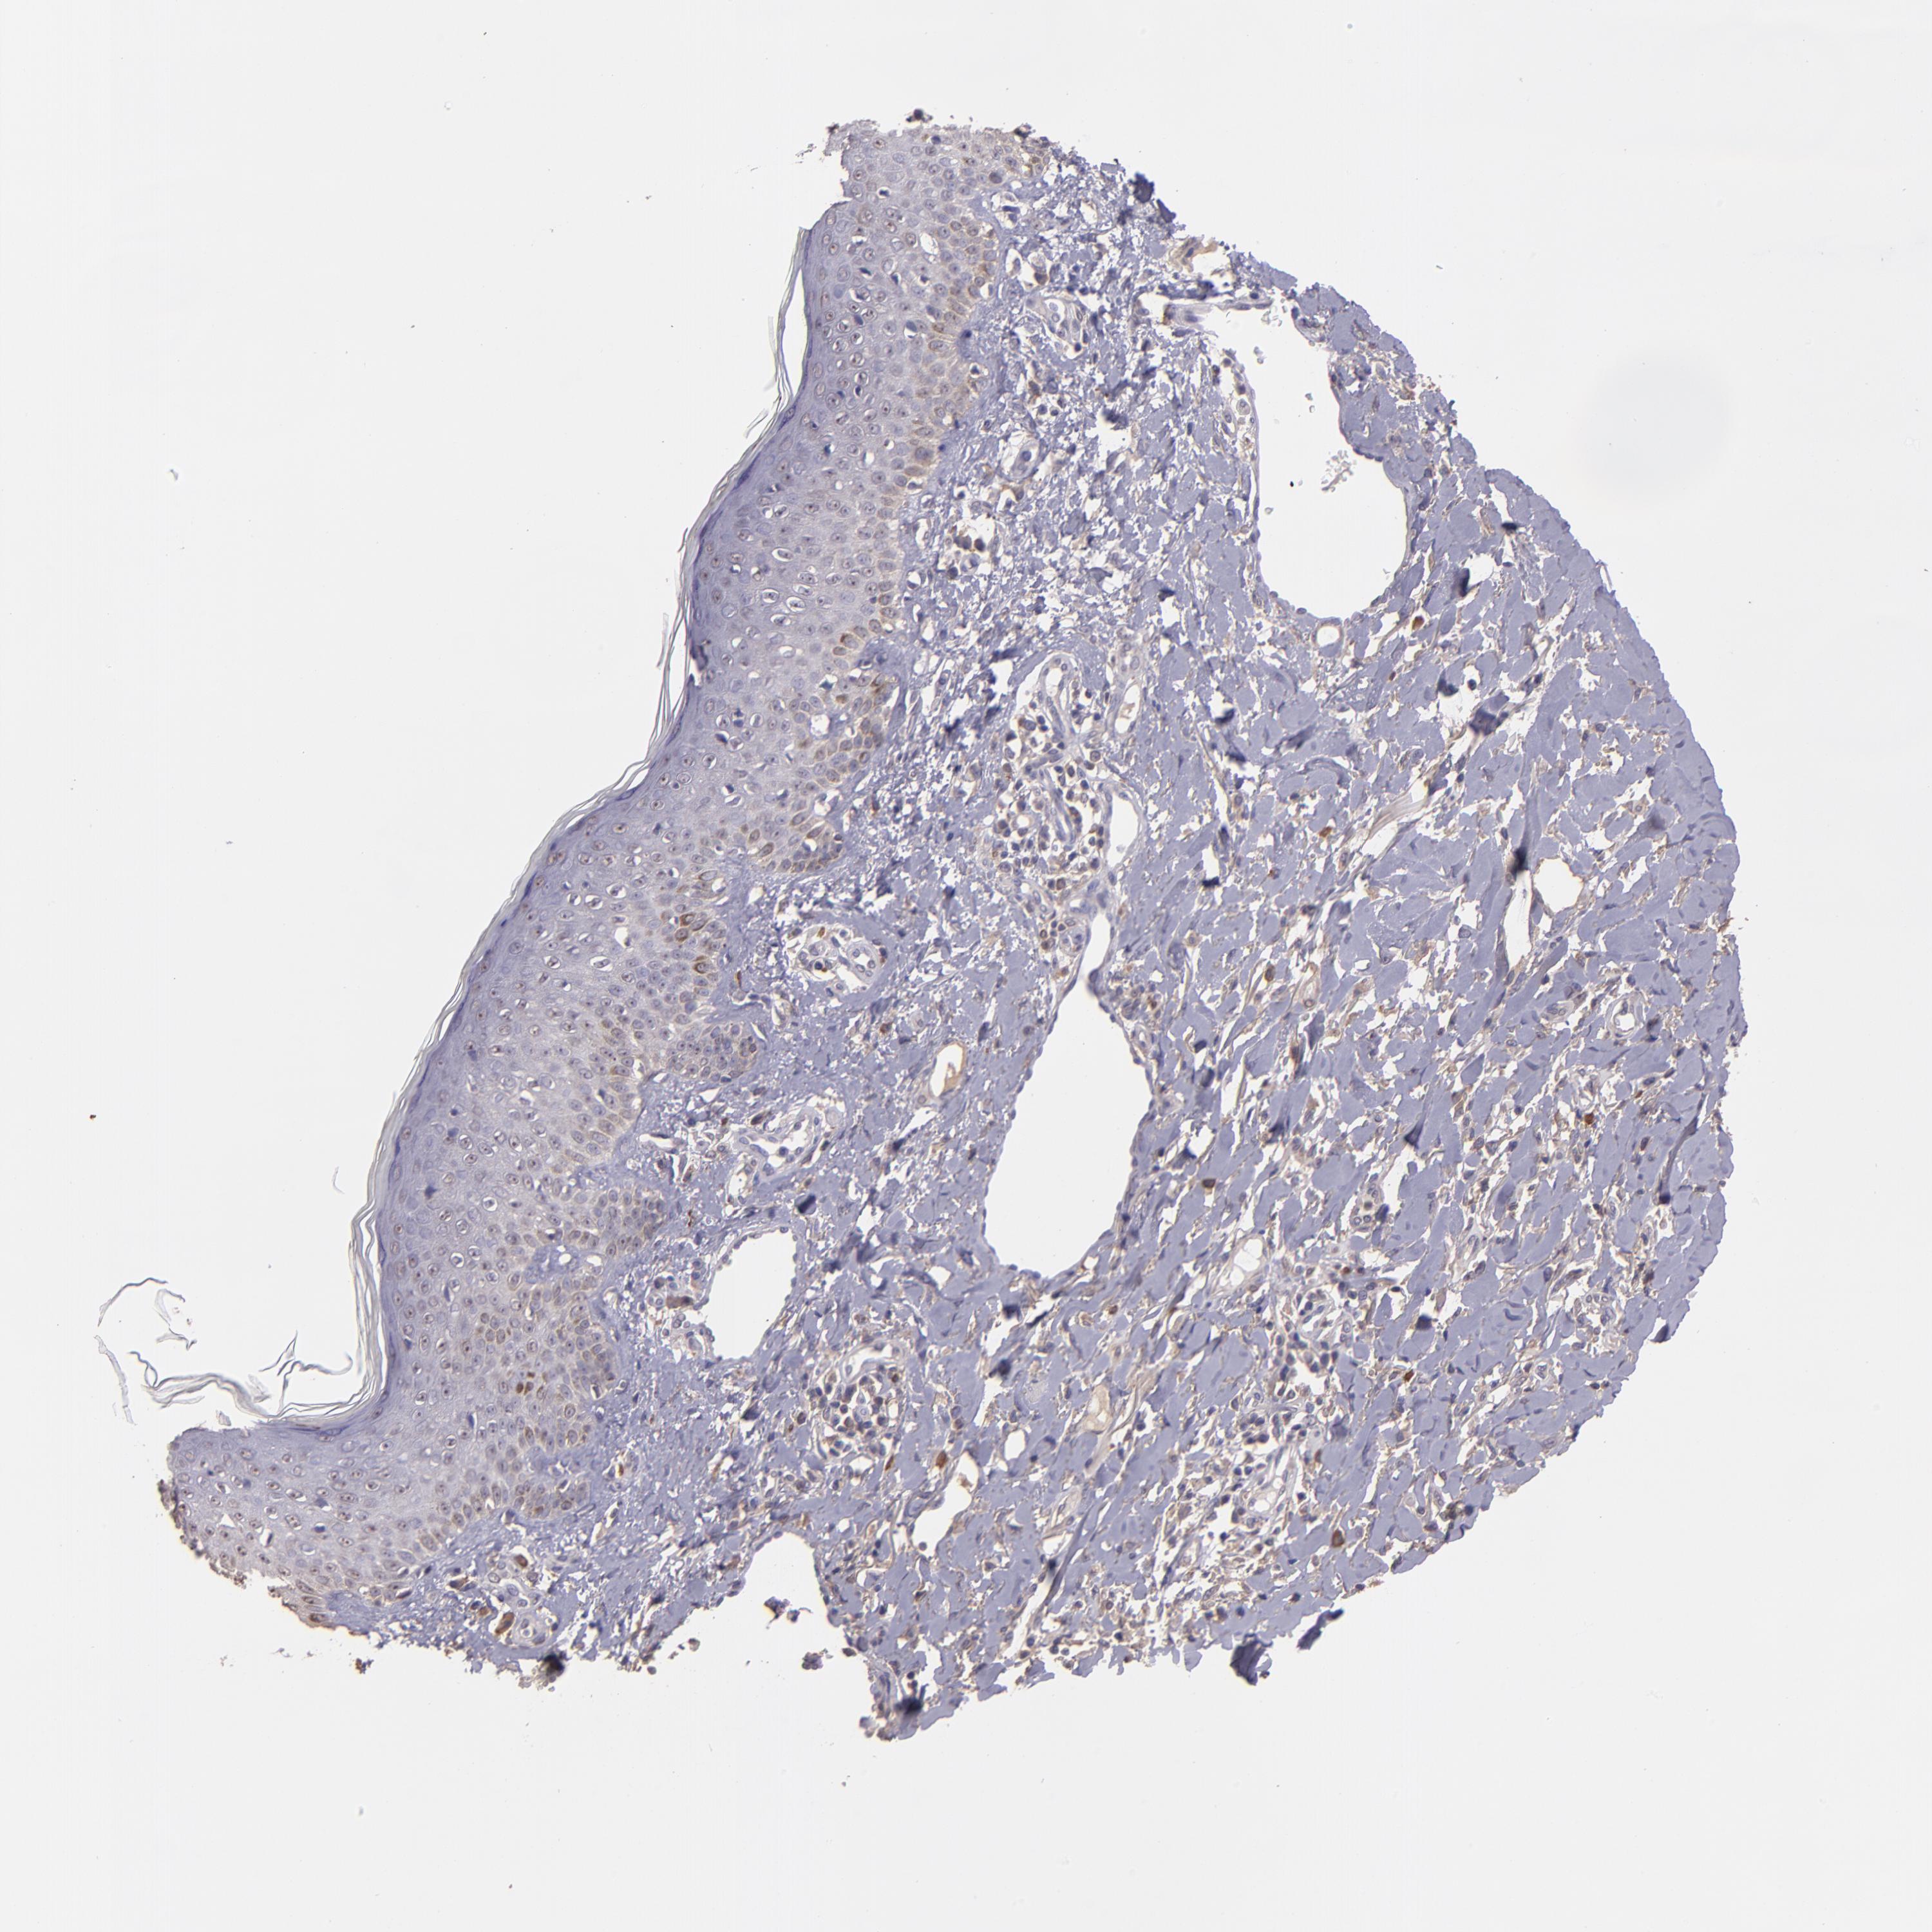

SKIN CANCER - Protein expressioni

A mouse-over function shows sample information and annotation data. Click on an image to view it in a full screen mode. Samples can be filtered based on level of antibody staining by selecting one or several of the following categories: high, medium, low and not detected. The assay and annotation is described here.

Antibody stainingi

Antibody staining in the annotated cell types in the current human tissue is reported as not detected, low, medium, or high, based on conventional immunohistochemistry profiling in selected tissues. This score is based on the combination of the staining intensity and fraction of stained cells.

Each image is clickable and will lead to virtual microscopy that enables deeper exploration of all samples and also displays staining intensity scores, fraction scores and subcellular localization as well as patient and tissue information for each sample.

Antibody HPA001667

Antibody CAB016724

Squamous cell carcinoma, NOS

Basal cell carcinoma

Squamous cell carcinoma, metastatic, NOS